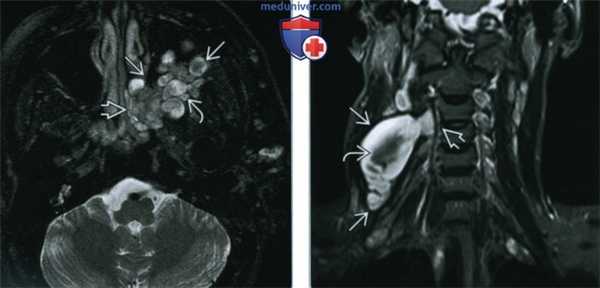

(Слева) Т2ВИ FS, аксиальная проекция, пациент с нейрофиброматозом 1 типа. Многодольчатое образование, деформирующее левую крылонебную ямку и распространяющееся в задние отделы полости носа через клиновидно-небное отверстие. «Признак мишени» в виде участка низкой интенсивности творит в пользу плексиформной нейрофибромы.

(Справа) STIR МРТ, коронарная проекция. Крупная плексиформная нейрофиброма правой половины шеи, происходящая из позвоночного отверстия С3-С4. В центре многодольчатого образования имеется классический «признак мишени» в виде участка низкой интенсивности.